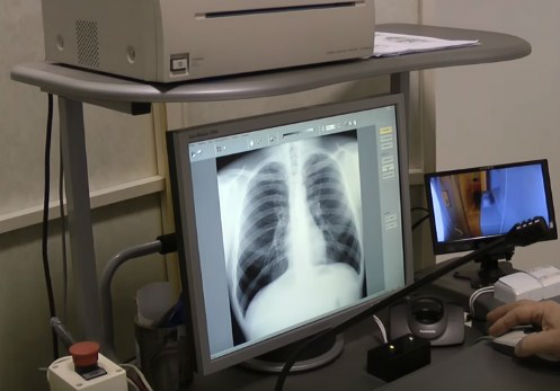

Для обследования жителей отдалённых населённых пунктов Бурятии будут работать передвижные флюорографы. В медицинских организациях Улан-Удэ и районах республики будут организованы дни открытых дверей.

- В республике широко внедряются инновационные методы диагностики и лечения больных туберкулёзом, позволяющие в ускоренном режиме устанавливать диагноз и в ранние сроки назначать лечение. Широко применяется внутрикожный диагностический тест – «Диаскинтест», предназначенный для повышения качества диагностики туберкулёзной инфекции у детей и подростков. Продолжается внедрение новых методов хирургического лечения туберкулёза лёгких и его осложнений, используются немедикаментозные малоинвазивные методы лечения, - отмечают в Республиканском центре медпрофилактики.